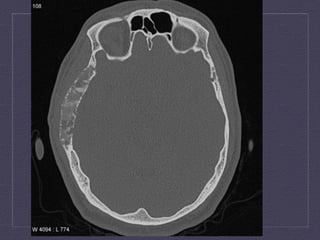

Axial  and  coronal  CT  demonstrates  septated,  ly:c  lesion  in  the   intertrochanteric  region  with  significant  thinning  of  the  posterior  cortex